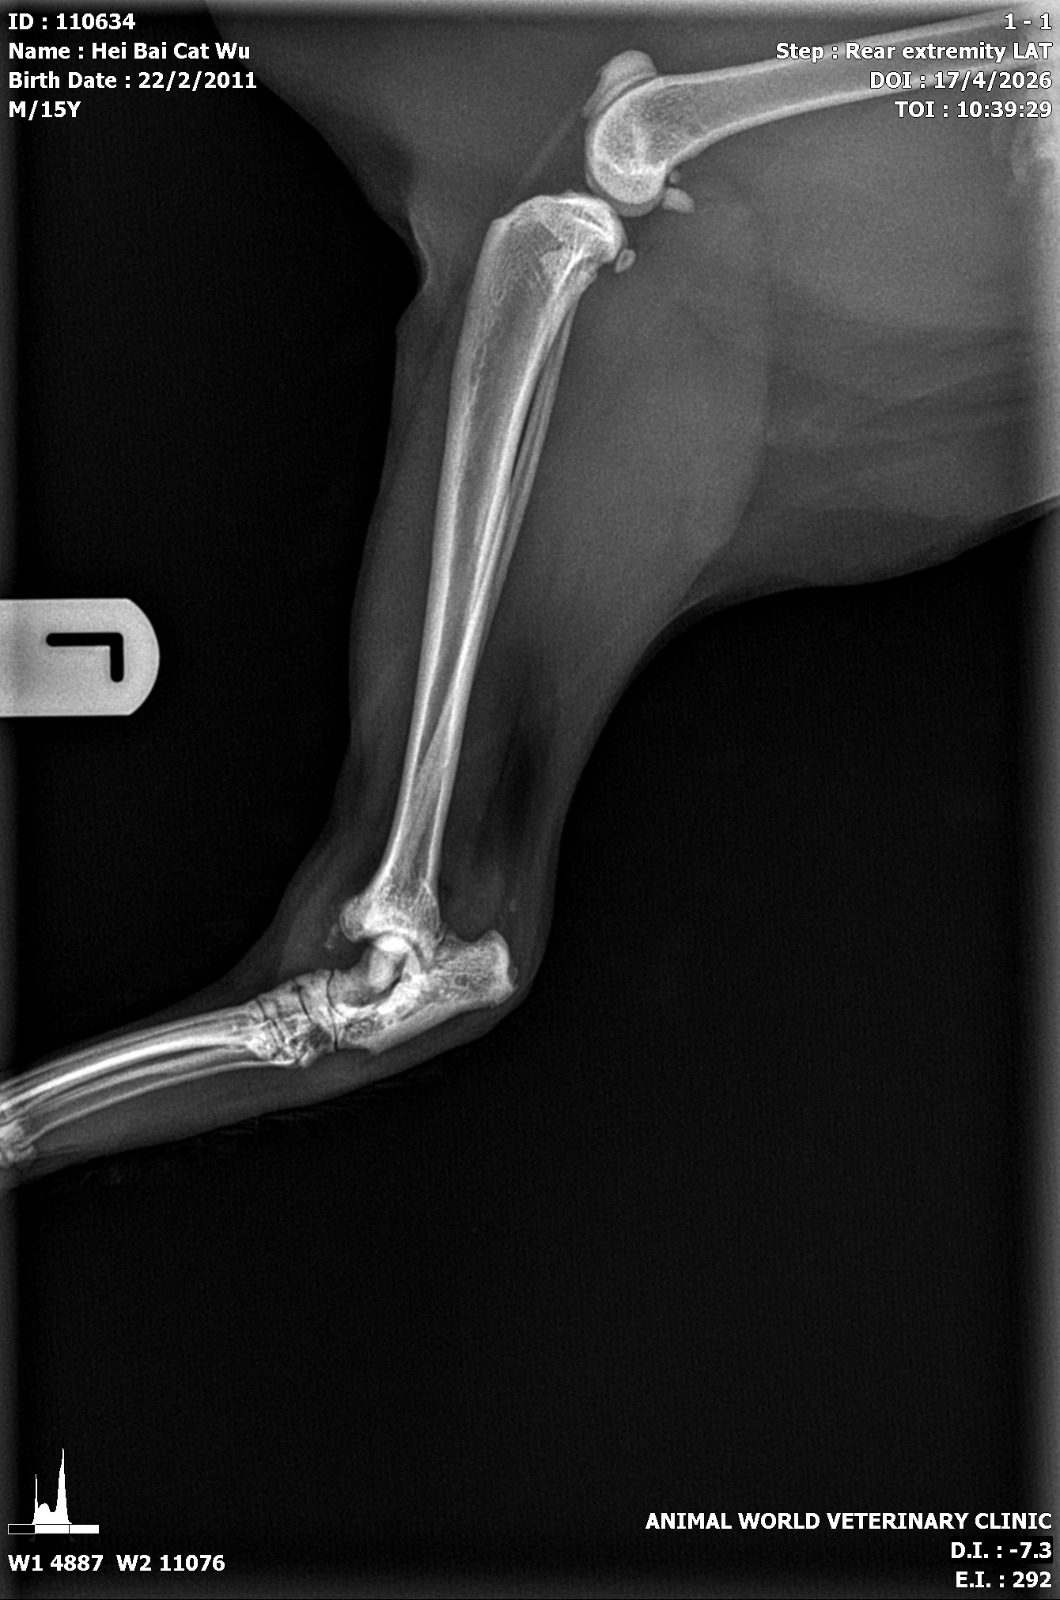

– xrays L and R hock all have evidence of marked arthritis and there is suspected fracture at the hinge of the hock (both left and right) so suspect is obesity related

– methadone given, can give 3-4days of melox to see if any improvement in swelling (mainly L hock)” – his HCT 48% and I’m correct, his kidneys r fine. But legs super not fine.

“i cannot to VD view of his legs cos he wont tolerate being upside down, ideally need la.”

“Right hock

Green arrows – osteophyte

Red arrow – suspected fractured site but ideally need VD view

Blue arrow – this lysis area in both legs”